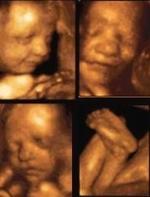

Lea esta lista y luego piense cuál de las siguientes posibilidades que ofrece la ciencia le parecen éticamente aceptables: una mujer de 63 años puede concebir un hijo sano que en realidad es su nieto; una pareja española selecciona el embrión de su futuro hijo para que pueda donar médula ósea a su hermano enfermo; una mujer sin hijos y enferma de cáncer congela sus óvulos para poder ser fertilizada con ellos dentro de una década, cuando haya superado las peligrosas y penosas consecuencias de la quimioterapia; una pareja de lesbianas engendra un retoño biológico de ambas.